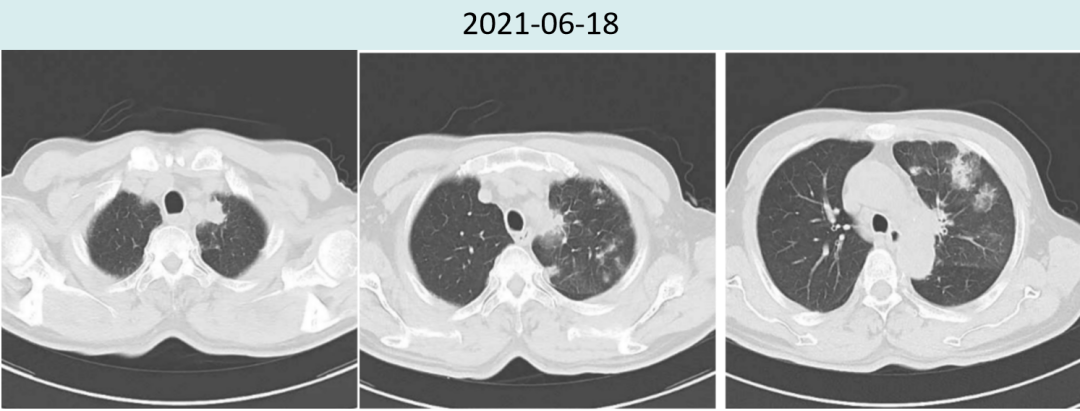

2021年6月18日治疗两周期后复查胸部CT提示:肿瘤较前明显缩小(4.5cm→2.0cm),新增多发炎性病灶,总体疗效评价为PR。

图1.患者治疗前后胸部病灶对比

图2.患者治疗前后肺炎情况对比